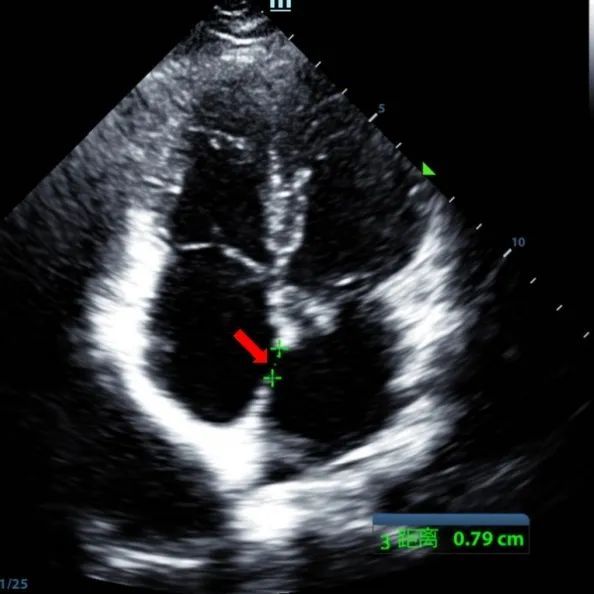

Laki-laki 9 tahun dengan secundum ASD (7.5-7.9mm) diperlakukan menggunakan MemoSorb BDASD-I 12mm occluber dan sistem pengiriman 12F. Tidak ada penyakit komplikasi atau komposit, pra-prosedur.

Serial echocardiographic follow-ups showed stable device position and favorable cardiac remodeling. Gradual degradation confirmed the occluder's long-term safety and efficacy.